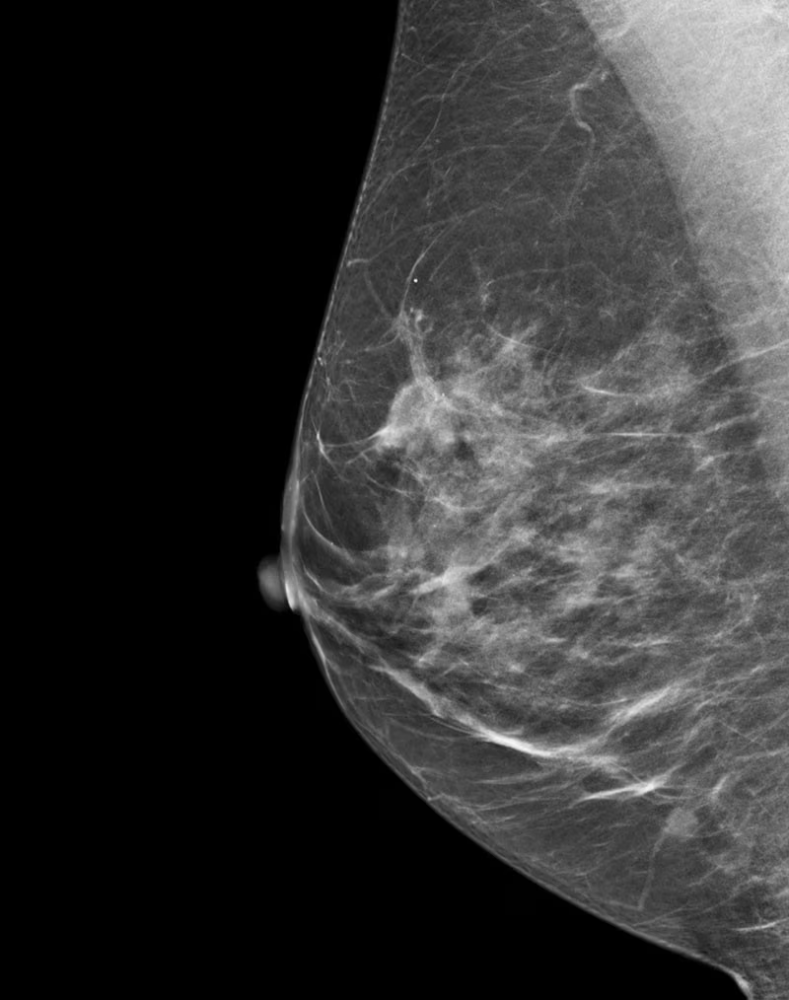

La Diagnostica Senologica dell'ospedale di Ortona aggiunge un nuovo tassello alla propria offerta. E' stata, infatti, attivata presso il Servizio di Radiologia Senologica la Mammografia con Mezzo di Contrasto, generalmente indicata come CEM (Contrast Enhanced Mammography).

Si tratta di una metodica innovativa avanzata in grado di fornire informazioni aggiuntive rispetto alla mammografia digitale standard e alla tomosintesi. Consiste consiste nell'eseguire una semplice mammografia previa infusione di mezzo di contrasto iodato, che permette di unire i principi della mammografia digitale stessa con quelli della utilizzati dalla Risonanza magnetica, con cui condivide un'elevata sensibilità e specificità . L'impiego del mezzo di contrasto è utile per determinare le dimensioni di una lesione tumorale o per identificare alcuni tipi in particolare, oppure, ancora, nello studio prima o dopo un trattamento chemioterapico per la valutazione di un eventuale residuo di malattia.

E' una procedura indolore e di semplice e rapida esecuzione che si propone come valida alternativa alla Risonanza magnetica della mammella, rispetto alla quale mostra i vantaggi di essere più rapida, meglio tollerata dalle pazienti ed anche molto meno costosa.

Attualmente viene eseguita in casi selezionati di donne con diagnosi di tumore della mammella in regime di ricovero programmato, previa valutazione del gruppo multidisciplinare di cure oncologiche della mammella.